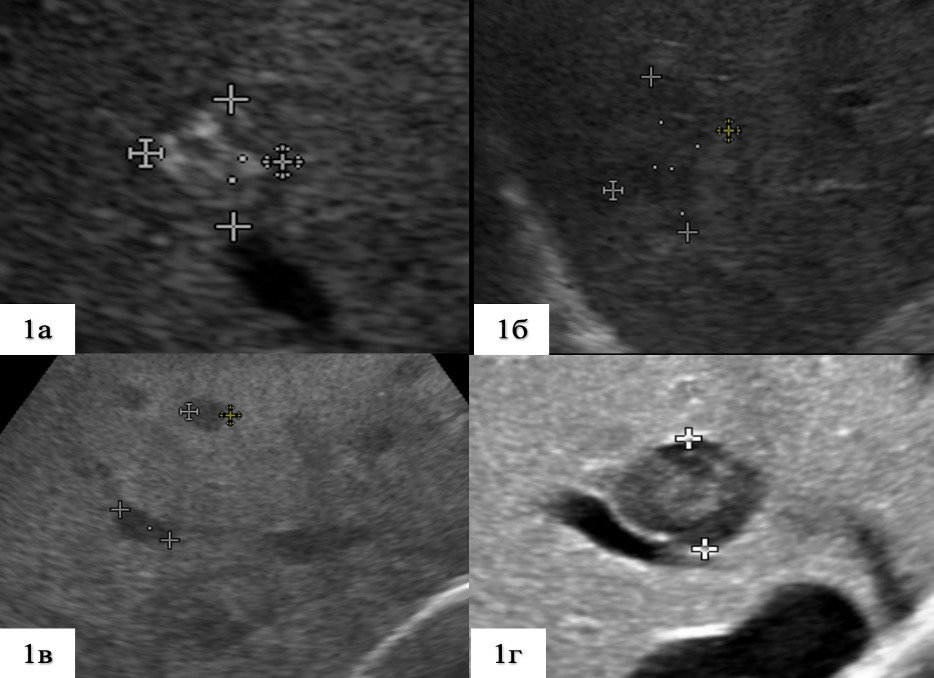

1. Рис 1. Типичные варианты ультразвуковой картины метастазов КРР в печень при УЗИ в серошкальном режиме | |